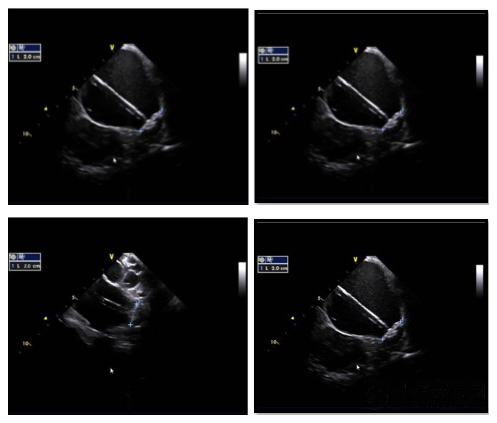

▲ICE下多角度測量評估封堵器壓縮比為16.7%平口封堵無殘余分流。

▲滿足PASS原則釋放封堵器完美完成LAAC手術。